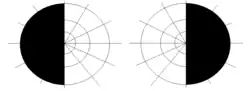

- A lesion involving complete optic chiasm, which disrupts the axons from the nasal field of both eyes, causes loss of vision of the right half of the right visual field and the left half of the left visual field.[3] This visual field defect is called as bitemporal hemianopia.

- Middle chiasmal syndrome, the lesions involving the decussating fibres in the body of chiasma produce bitemporal hemianopia.[1]

- Lateral chiasmal lesions may produce binasal hemianopia.[1]